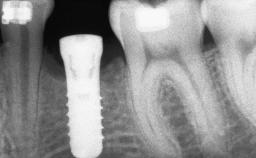

Ridge Preservation and Implant Placement for a Fixed Dental Prosthesis After a Car Accident

It is well known to clinicians that any removal of teeth will, over time, cause the dimensions of the alveolar ridge to be reduced by resorption of the bundle bone and by changes related to external modeling. This development is particularly evident in the crestal region with its thin buccal bone that consists of bundle bone almost entirely. The facial bone will rapidly resorb as blood supply from the periodontal ligament gets disrupted (Araújo and Lindhe 2005). There is no reason why traumatic tooth loss should not have the same consequences. It takes more than achieving implant osseointegration for a treatment outcome to be considered successful. No deficiency of bone or soft tissue is acceptable when an ideal esthetic outcome is the goal. Several articles (Sanz and coworkers 2011; Vignoletti and coworkers 2011) have reported on techniques of improving the alveolar ridge for implant treatment, notably focusing on protecting tissues from resorption.

# of Implants 4

Type of Implants One-Piece|Reduced-Diameter

Bone Augmentation Horizontal|Simultaneous|Sinus Floor Elevation|Staged